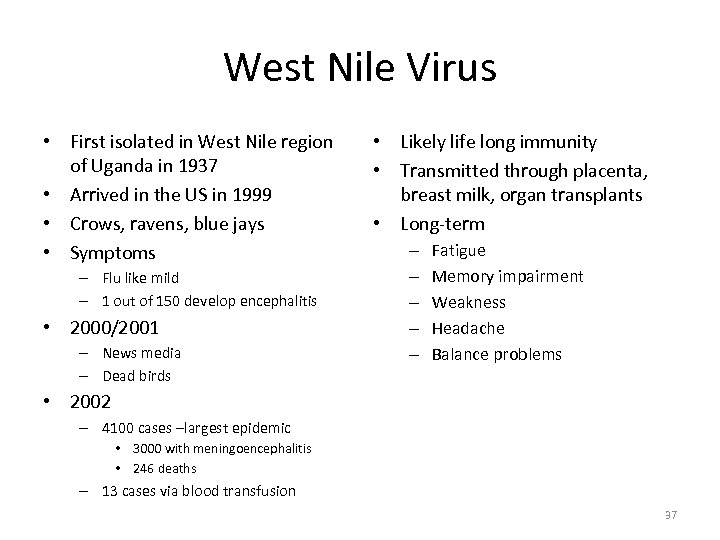

West Nile Virus • First isolated in West Nile region of Uganda in 1937 • Arrived in the US in 1999 • Crows, ravens, blue jays • Symptoms – Flu like mild – 1 out of 150 develop encephalitis • 2000/2001 – News media – Dead birds • Likely life long immunity • Transmitted through placenta, breast milk, organ transplants • Long-term – – – Fatigue Memory impairment Weakness Headache Balance problems • 2002 – 4100 cases –largest epidemic • 3000 with meningoencephalitis • 246 deaths – 13 cases via blood transfusion 37